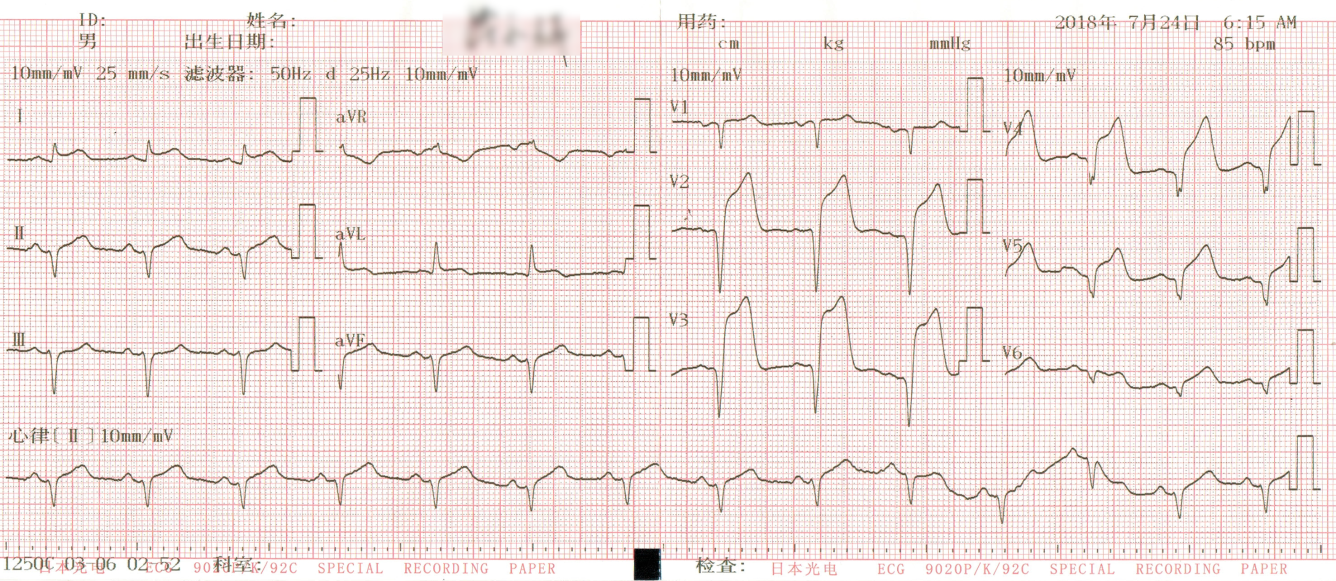

2008年,荷兰鹿特丹心内科医师De winter等[1]在《新英格兰杂志》上发表了一篇文章,引起了心血管医师的注意,该研究通过回顾其心脏中心1 532例左前降支近段闭塞的急性冠脉综合征患者的心电图时发现,30例并未出现典型ST段抬高的心电图改变,而是表现为胸前V1-6导联J点压低1~3 mm,ST段呈上斜型下移,T波对称高尖,QRS波通常不宽或轻度增宽,部分患者胸前导联R波递增不良,多数患者aVR导联ST段轻度抬高,后来这一类疾病被命名为De winter综合征。也正因为心电图的不典型,未引起临床医师的重视,从而导致De winter综合征患者未及时得到诊治。目前关于De winter综合征的文献多为个案报道[2-3],笔者收集De winter综合征患者7例,现报道如下。

2 结果 本研究收集7例De winter综合征患者,6例进行了急诊冠脉造影,胸痛至球囊扩张平均时间为3.3 h,1例进行择期冠脉造影。其中,3例为前降支近段严重病变,1例为第一对角支闭塞,3例为前降支中段闭塞,2例合并多支血管病变,5例为单支血管病变,均行前降支支架植入术(表 4)。1周内行心脏彩超检查,4例出现室壁运动减弱,2例EF值小于50%,2例心脏形态结构未见异常,1例患者术后第2天因个人原因自动出院,未完善心脏彩超(表 5)。观察7例患者住院期间心电图演变情况,其中有3例在PCI术后出现前壁导联ST段抬高,4例未出现ST段抬高(表 5)。病例1住院期间出现室性心动过速,病例7患在急诊科就诊时发生呼吸心搏骤停,经抢救后送导管室行急诊冠脉造影。另外,所有患者经药物及介入治疗后,均症状缓解出院,院外长期服用阿司匹林100 mg/d+替格瑞洛90 mg/12 h+阿托伐他汀40 mg/瑞舒伐他汀20 mg等药物,出院1个月后电话随访,7例患者均无胸痛、气促发作及再住院,无死亡病例。

表 5 7例患者的心电图演变及心脏彩超结果

3 讨论 De winter综合征是近10年来新发现的心电图诊断,其诊断标准为:⑴胸前导联T波高尖对称; ⑵胸前V1-6导联J点压低1~3 mm,ST段呈上斜型下移; ⑶QRS波群通常不增宽或轻度增宽; ⑷可出现胸前导联R波递增不良; 大多数患者aVR导联ST段抬高1~2 mm。当然,这仅是心电图诊断,具体还要结合临床及其他辅助检查。目前其已被证实与前降支急性闭塞有关,占急性前壁心肌梗死的2%。虽然De winter综合征不属于STEMI范畴,但因其心血管事件的发生风险较高,有学者提出,其治疗时机应参照STEMI,尽早行冠脉造影及干预靶血管,改善预后。本文7例De winter综合征病例中,6例患者行急诊冠脉造影+PCI术,术后心脏彩超证实4例患者心功能恢复良好,1例(病例1)心脏收缩功能受到影响(EF 35%),恰巧该患者PCI术后心电图也演变为STEMI,是否演变为STEMI的De winter综合征患者的心功能较未演变为STEMI的患者更容易受损,有待于进一步证实。1例(病例5)择期冠脉造影+PCI术患者心功能明显受损,这可能与缺血时间长,心肌细胞损伤严重有关。另外,住院期间心血管事件发生、30 d再住院、死亡等方面,7例患者预后均良好。

De winter综合征的主要心电图改变为:胸前V1-V6导联ST段呈上斜型下移,T波对称高尖,多数患者aVR导联ST段轻度上抬。出现这种心电图改变的原因尚未清楚。传统观点认为ST段压低,是因为心肌细胞受损后,由于不能正常除、复极,导致正常与异常心肌细胞之间产生电位差,出现损伤电流,导致ST段出现了相对或直接偏移。近年来,有人提出离子流学说,正常时Ito电流分布为外膜>内膜,当心内膜心肌缺血时,内膜Ito电流明显增大,达到钙失活电位后,造成二相平台丢失,内外膜之间形成的电位差由高到低指向心内膜,背离探查电极,从而引起ST段压低[5]。刘元生[6]则认为,前壁导联ST段未抬高,可能与细胞膜上ATP敏感性钾通道(KATP)不能激活有关,其机制是心肌缺血使ATP产生缺乏。也有学者推测可能是反复心肌缺血,及各冠脉之间已形成广泛的侧支循环所致[7]。

De winter综合征表现为T波高尖,临床上应注意与急性心肌梗死超急性期、高钾等疾病相鉴别。有学者认为,De winter综合征不会演变成STEMI,与STEMI超急性期的鉴别关键在于密切监测心电图,如果是De winter综合征,其ST段不会抬高,而急性心肌梗死超急性期心电图会有动态演变,T波高尖之后会逐渐出现ST段抬高,R波下降甚至丢失,病理性Q波形成等特点,但这种观点与本研究观察到的情况不符,本文中病例1、病例5和病例6都观察到心电图演变为STEMI。临床上观察不到的原因可能是:⑴患者发病时间短,心电图还来不及演变为ST段抬高,就已行冠脉造影及支架植入开通血管。⑵ST段抬高可能是一过性的,开通血管后ST段又回落至基线。只有密切监测心电图,才可能真正发现问题。至于与高钾导致的T波高尖的鉴别,急查血清钾即可明确。De winter等[1]发现心电图表现为ST段上斜型压低,T波高尖的患者,冠脉造影均提示前降支近段闭塞,且为单支血管病变。本文中观察到,3例为前降支近段严重病变,1例为第一对角支闭塞,3例为前降支中段闭塞,2例合并多支血管病变,5例为单支血管病变。亦有研究发现,心电图表现为De winter综合征,但冠脉造影却提示左主干闭塞[8]。可见,本文的发现及Murat等[8]的发现提示De winter综合征的靶病变不一定局限于LAD近段。另外,从本文观察到的情况,患者发病年龄都相对年轻,且均为男性,2例合并高脂血症,与以往文献报道[9]相符。